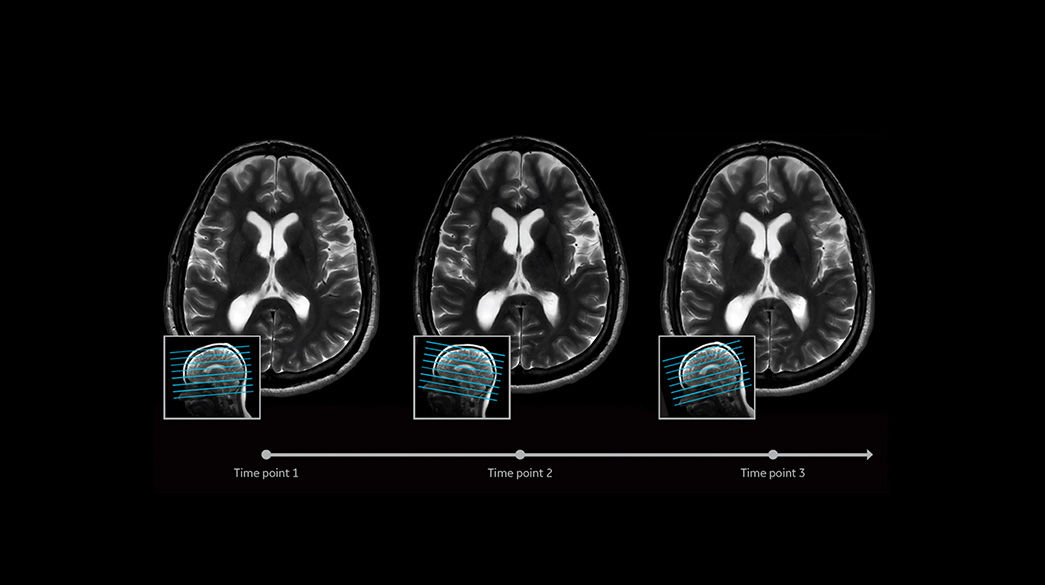

Consistent

Motion and distortion-reduced scans with high-resolution and contrast

Diagnostic confidence and consistency